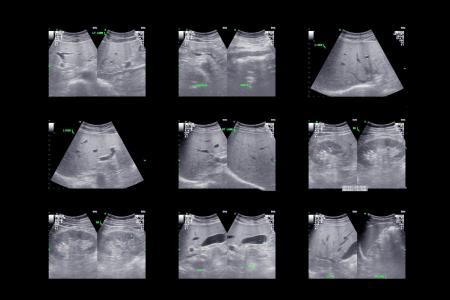

Coup d’accélérateur pour la formation à l’ultrasonographie ciblée

Réalisée au lit du malade, cette méthode diagnostique non invasive et non irradiante est utilisée comme un complément à l’évaluation des patients et des patientes.